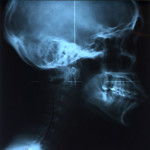

If it’s your first time to go to an upper cervical chiropractor, you’ll need an average of 8 to 12 visits, then the doctor will re-assess you for lifetime treatment. The first session involves a general assessment of your health, habits, and posture, followed by three x-rays (from the side, front, and top of head and neck) specific to the practice of upper cervical chiropractic. This is usually the longest session. The doctor will then study your x-rays, posture, and result of the initial consultation, and based on all these will determine if you need an atlas or spine adjustment on your next visit.

Side of head